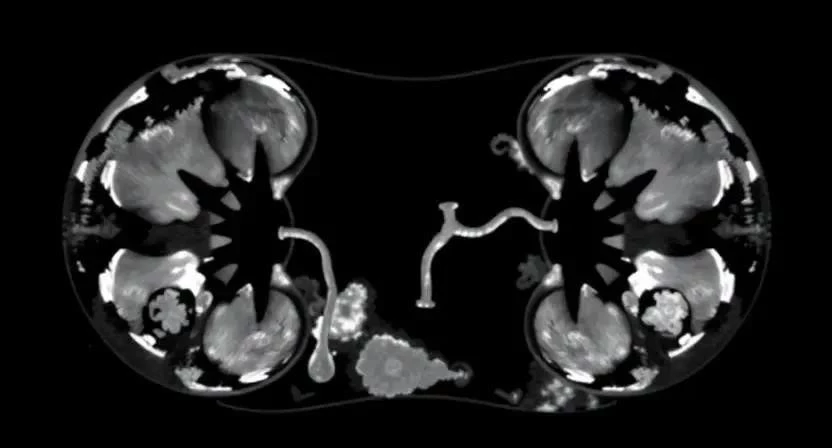

Визуализация почек – это использование различных методов для получения изображений почек и мочевыводящих путей. Это необходимо для выявления структурных изменений, оценки кровотока и определения функциональных возможностей почек. Целью визуализации является диагностика заболеваний, контроль эффективности лечения и оценка состояния почек перед хирургическим вмешательством.

Ультразвуковое исследование (УЗИ)

УЗИ почек – это неинвазивный и безопасный метод, использующий звуковые волны для создания изображения почек. Подготовка к УЗИ обычно не требует специальных мер, но в некоторых случаях может быть рекомендовано пить достаточное количество жидкости для заполнения мочевого пузыря. Во время процедуры на кожу наносится гель, а затем по ней перемещается датчик. УЗИ позволяет оценить размер, форму и структуру почек, выявить камни, кисты и другие образования. Оно также может использоваться для оценки проходимости мочеточников.

КФ МРТ (магнитно-резонансная томография)

КФ МРТ – это новый метод визуализации почек, позволяющий получить детальные изображения клубочков почек. Этот метод особенно полезен для диагностики гломерулонефрита и других заболеваний, поражающих клубочки. КФ МРТ обладает высокой чувствительностью и специфичностью, что позволяет точно определить степень поражения клубочков и оценить функцию почек. Преимущества КФ МРТ заключаются в отсутствии ионизирующего излучения и возможности получения высококачественных изображений.